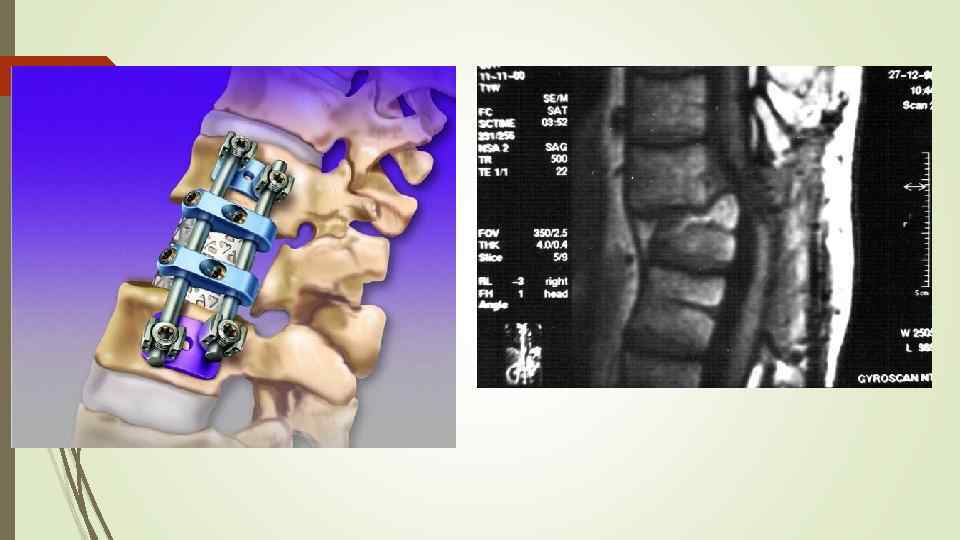

Вертебропластика и фибропластика относятся к современным методам лечения компрессионного перелома позвоночника. Такие методы позволяют более эффективно устранять повреждения костной ткани, что значительно снижает время лечения и реабилитации компрессионного перелома позвоночника.

Кифопластика – это такой метод лечения компрессионного перелома позвоночника, при котором сначала восстанавливается нормальная высота повреждённого позвонка, а затем вводится цементирующий раствор. Такой метод лечения восстанавливает позвонок в его нормальном положении.